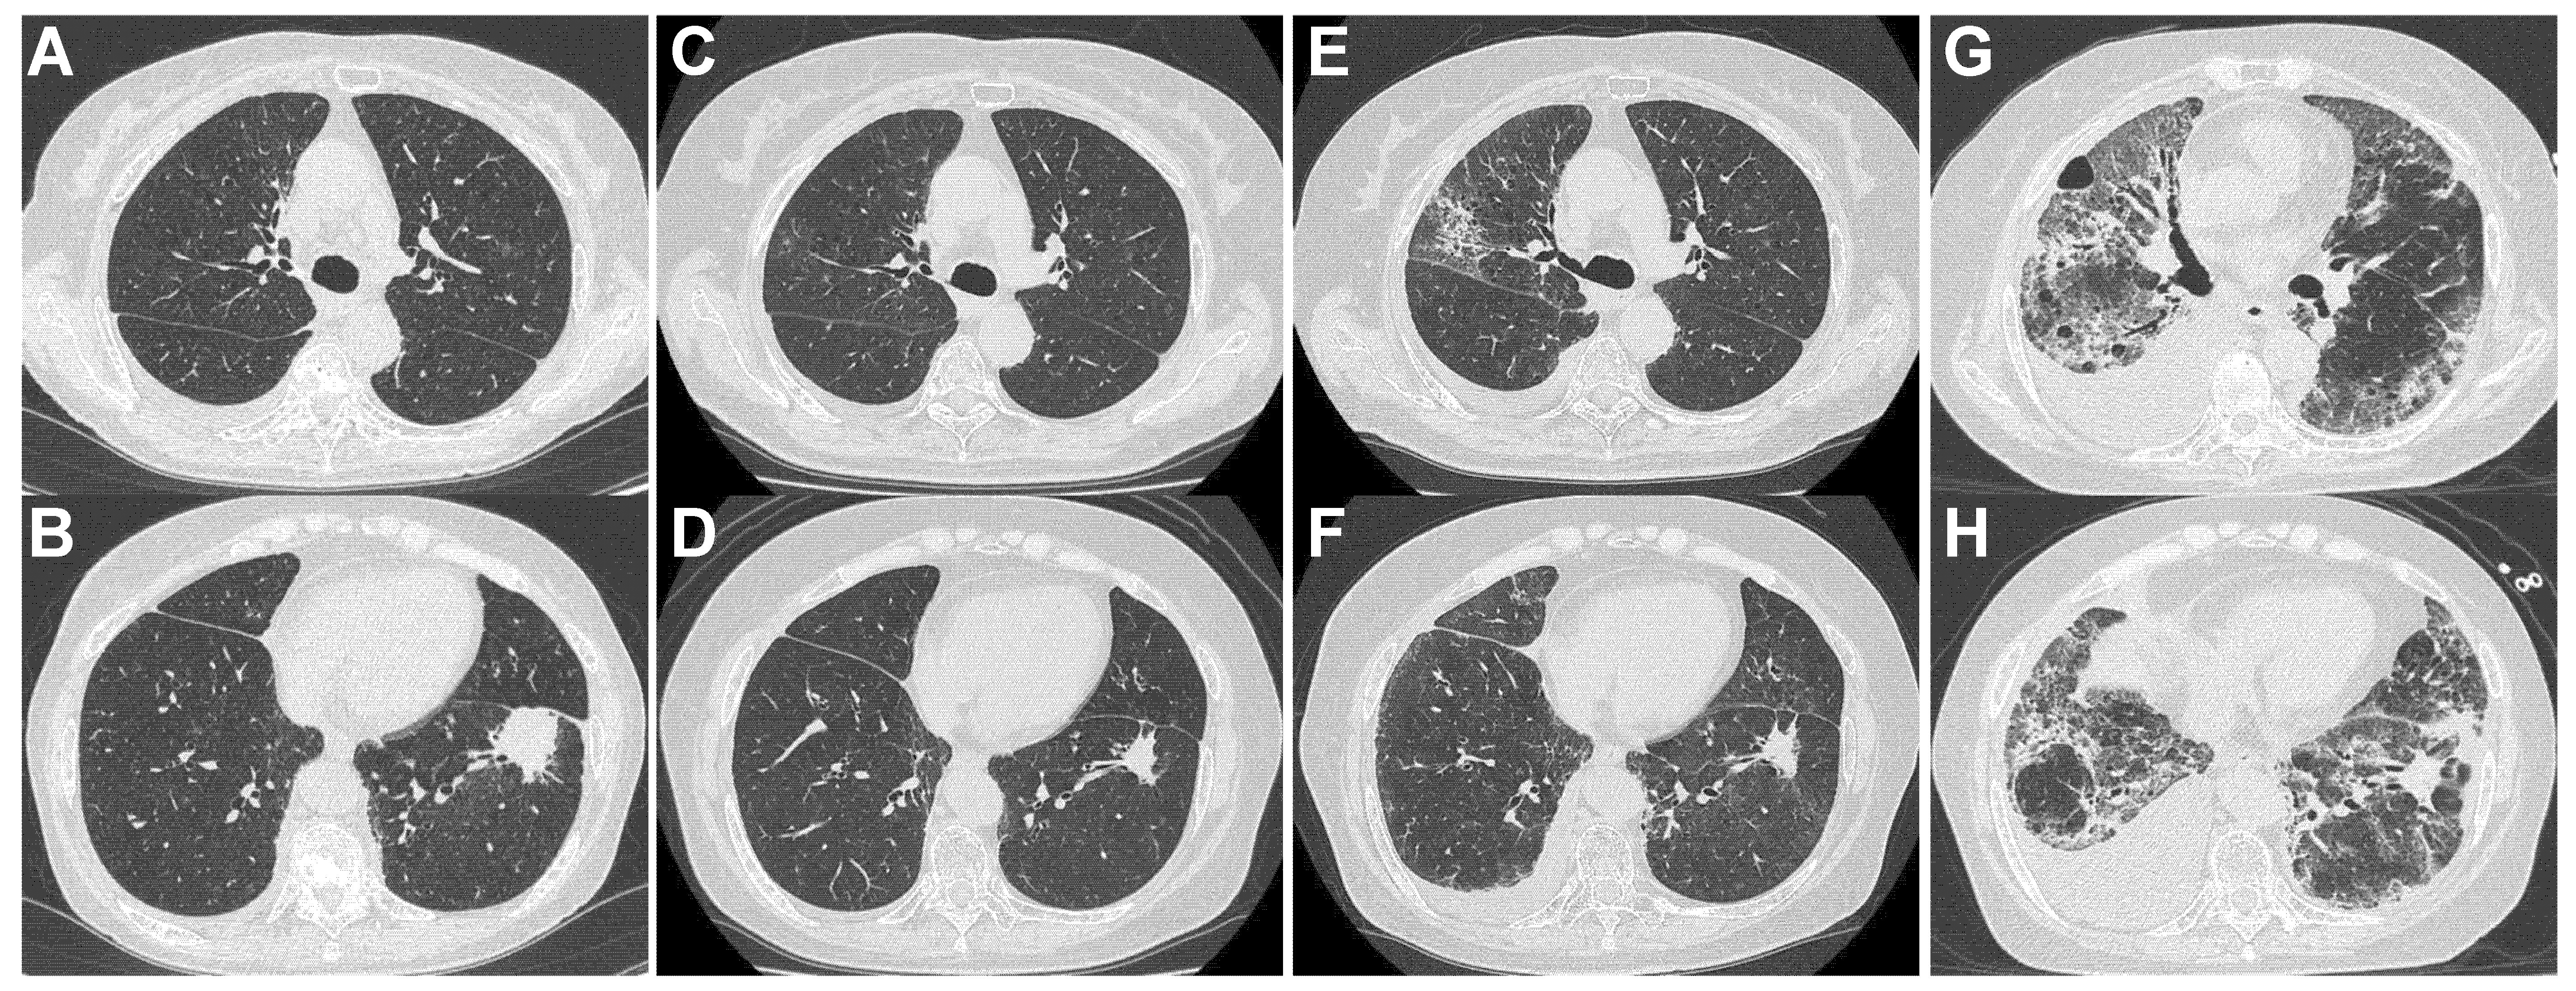

4.4.1. Patient 1 (Figure 2, Table 4)

4.4.2. Patient 2 (Figure 3, Table 4)